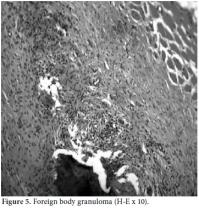

A 10-year-old boy was referred to the Pediatric Rheumatology Unit at the University Hospital Federal University of Pernambuco, Recife in 2008 with a fiveyear history of intermittent pain in his left clavicle, right hip, ankles, and dorsal spine. In 2006, he was admitted to the Pediatric Unit complaining of back pain, fever, and a mass over his left clavicle. Blood tests showed a C-reactive protein (CRP) level of 24 mg/dl and an erythrocyte sedimentation rate (ESR) of 39 mm/h. A chest X-ray confirmed the mass over his left clavicle (Figure 1). Septic osteomyelitis was diagnosed, although his blood and bone cultures were negative. A course of an empirical antibiotic (cephalothin) and NSAIDs was prescribed. He was later referred (after one year) to the Orthopedic Unit where a thoracic computed tomography (CT) scan showed the volume of the left clavicle had increased due to an area of hyperostosis mixed with osteolysis. Hence, the antibiotic was changed to ciprofloxacin for three months. As there was no improvement, he was referred to the Pediatric Rheumatology Unit, where a tuberculin test and ANA were negative. A bone scan showed an increased technetium-99m (99mTc) radioisotope uptake at the left clavicle, ankle, sacroiliac joints, and T8 thoracic disc (Figure 2). Magnetic resonance imaging (MRI) demonstrated multiple inflammatory lesions between the T7 and T9 disks (Figure 3) and in the left clavicle and left ankle (Figure 4), thus confirming the findings on the bone scan and thorax CT. The results of the histological analysis of a bone biopsy were compatible with aseptic chronic osteomyelitis (Figure 5). No infection was identified by lesion or blood culture, and no malignancy was detected by imaging; hence, the possibility of CRMO was raised. An aggressive treatment with NSAIDs, alendronate 70 mg/week, methotrexate 15 mg/week, and infliximab 5 mg/kg was initiated due to the severity of the case and the delay in diagnosis. After the third infusion of infliximab, the boy became free of pain. His ESR and CRP levels were normal, and a bone scan showed a tiny uptake at the left clavicle. It should be noted that the patient and his family gave their consent for any treatment provided at the Pediatric Rheumatology Unit.

A bone biopsy is necessary for the differential diagnosis of CRMO in order to exclude malignancy and infection, and pyogenic osteomyelitis, if found, is a reliable indicator of this disease. Usually an extensive microbial investigation (including tissue culture and serology) should be conducted since treatment with antibiotics is ineffective. However, improvement in patients treated with azithromycin has been reported, but this can be attributed to its anti-inflammatory effect.[14] The biopsy of the clavicle in our case showed a chronic inflammatory reaction like that of a foreign body granuloma.